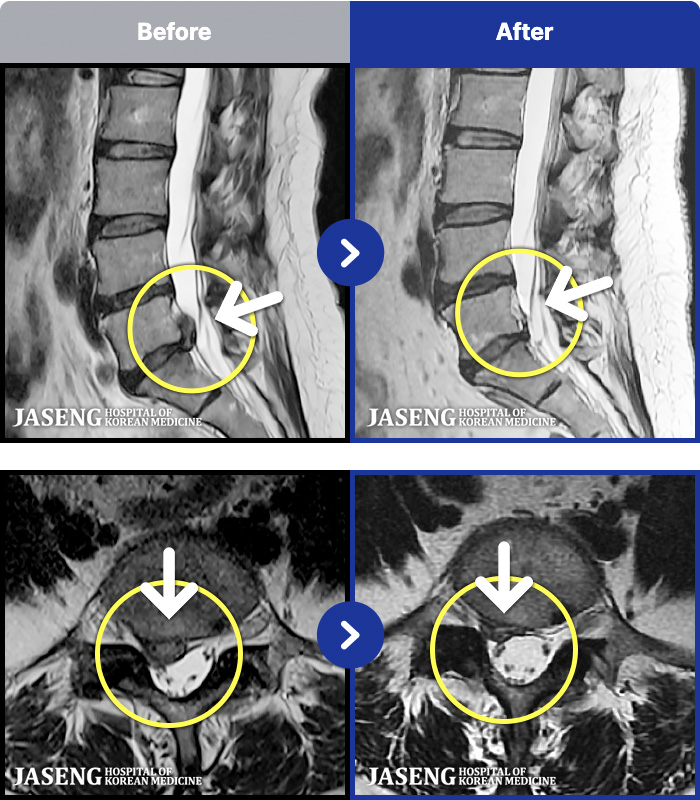

ȯںп Ǹ ǿ ԿǾ, ο ġ ۿ Ƿ ġḦ Ͻñ ٶϴ.